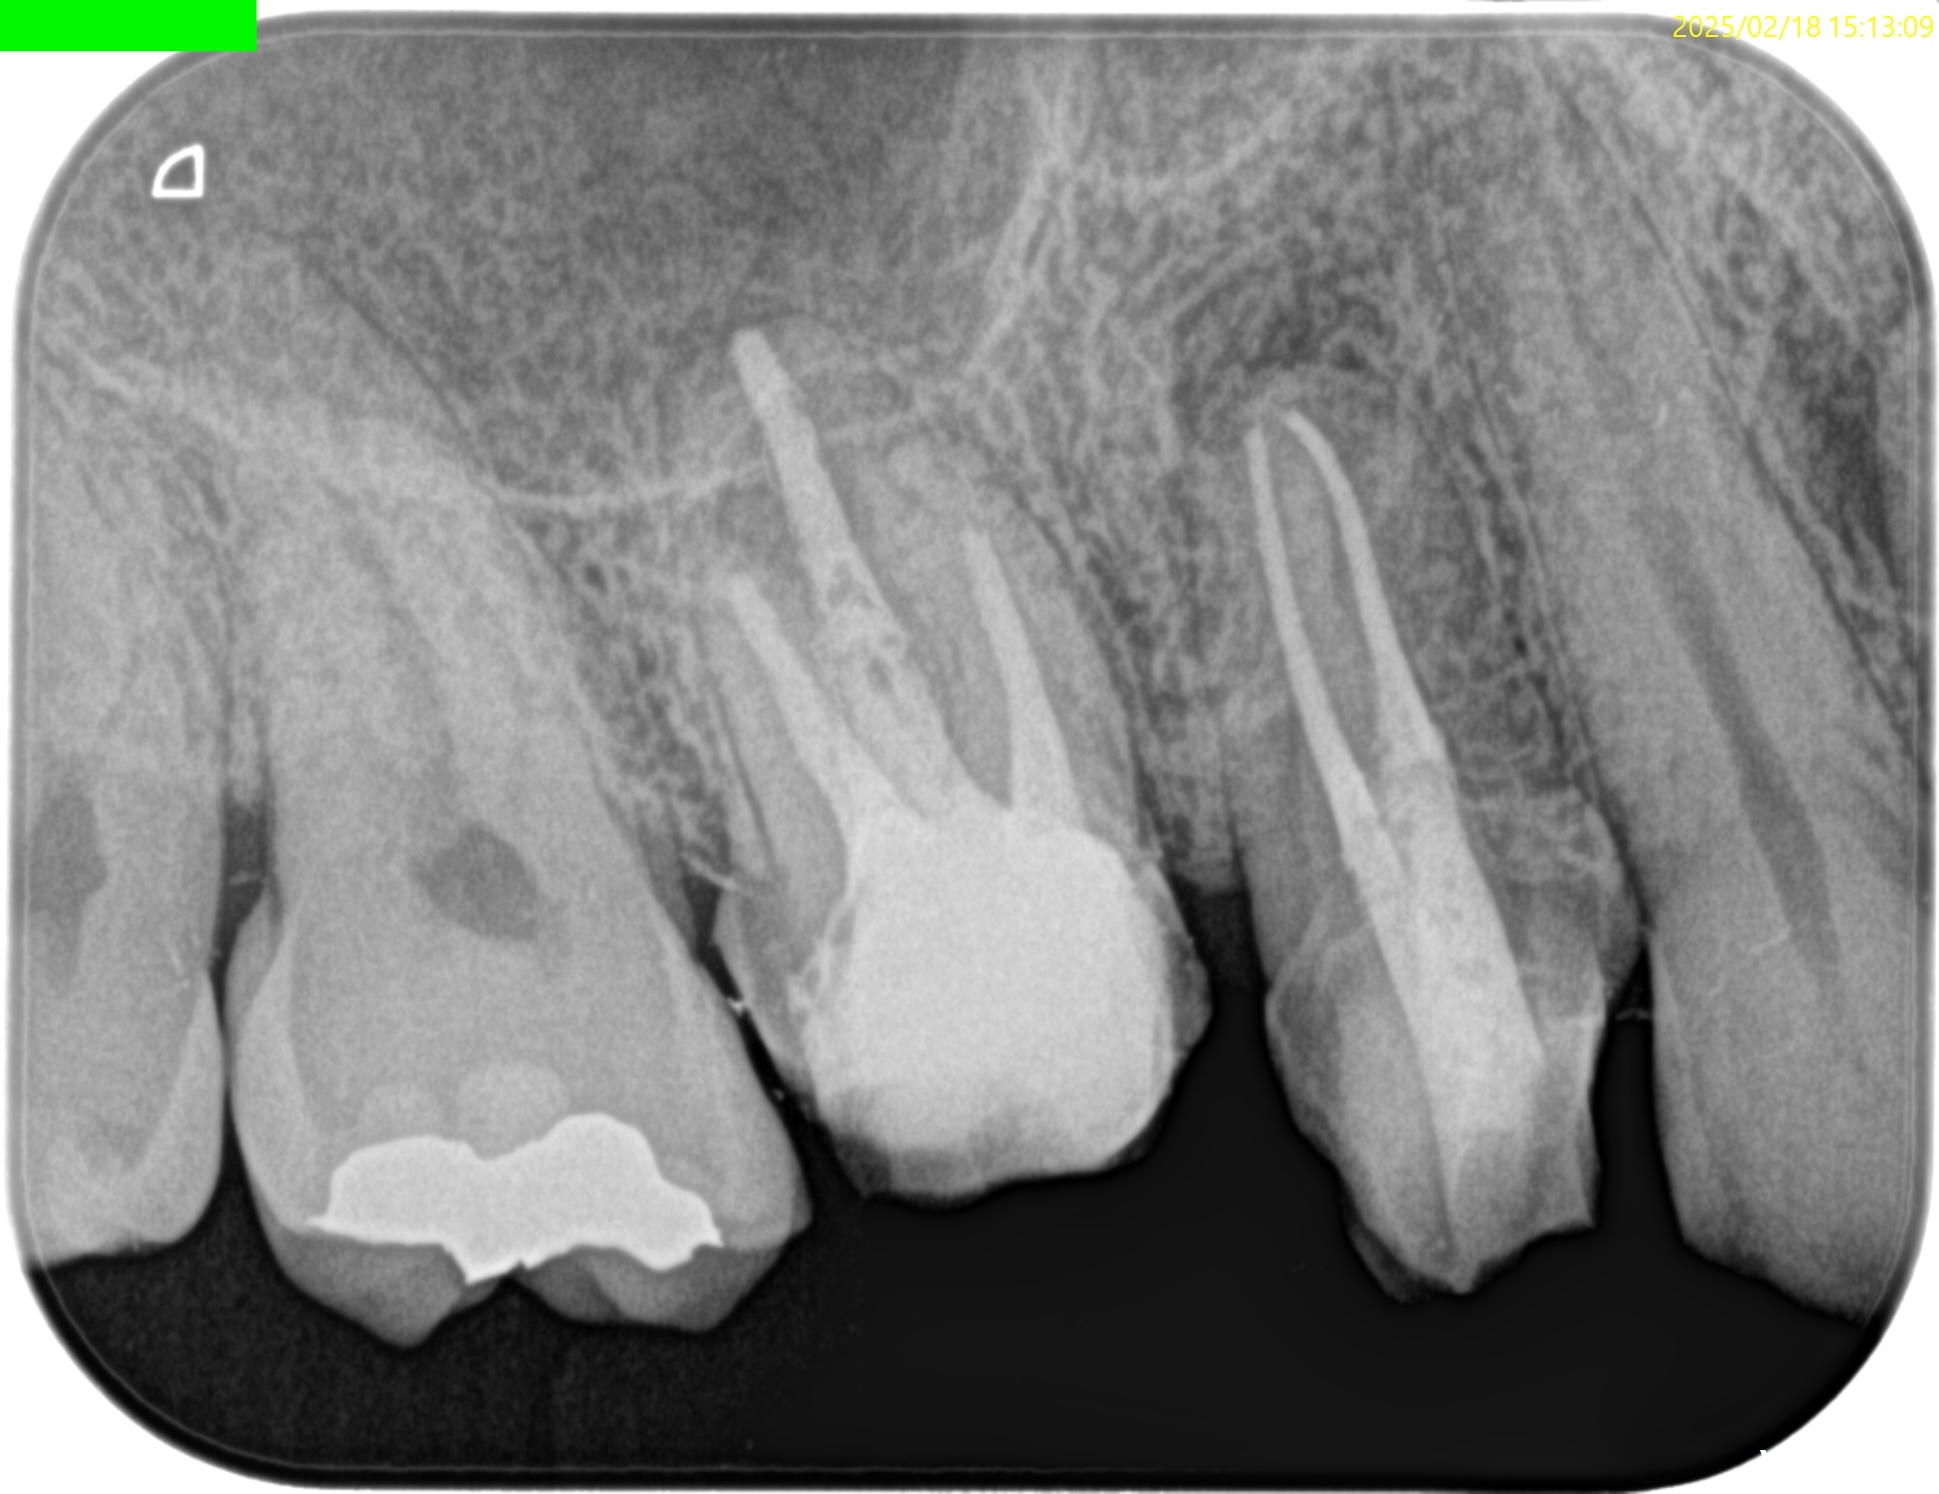

まず、#3 Pのみ再根管治療を行い(2025.2.18)、

充填後、CBCTとPAを撮影した。

問題はないだろう。